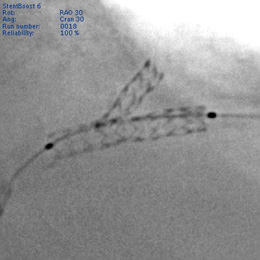

●StentBoost(図2)

心臓領域に留置されたステントを,あたかも静止しているかのように描出する画期的な技術です。撮影後わずか数秒で視認性の向上したステント画像が,検査室内のモニタに表示されます。ステント拡張後の確認はもちろん,造影画像とのサブトラクション処理を行うことで,血管との位置関係の把握も容易になりました。

図2 StentBoost画像